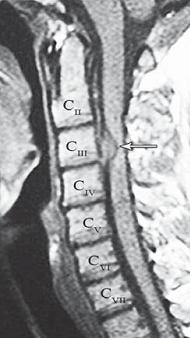

МРТ № 1

На магнитно-резонансной томографии (МРТ) № 1 — шейный отдел позвоночника, в относительно нормальном состоянии.

Шейный отдел позвоночника должен иметь нормально выраженный физиологический лордоз, не должно быть гиполордоза или гиперлордоза, а так же кифотических деформаций.

Ширина спинного мозга: сагиттально > 6–7 мм

1. Сагиттальный размер позвоночного канала на уровне:

СI 21 мм

СII 20 мм

СIII 17 мм

CIV-CVII = 14 мм

2. Высота межпозвонковых пространств:

СII < СIII < СIV < СV < СVII  СVII

3. Ширина спинномозгового канала: поперечный диаметр на уровне ножек: > 20–21 мм